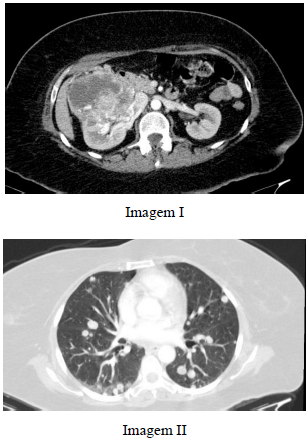

Paciente do sexo masculino, com 37 anos de idade, após cair de uma árvore de 6 m de altura, refere dor lombar à esquerda e hematúria. Realizou tomografia computadorizada de abdome, que evidenciou as imagens I e II a seguir.

A imagem I demonstra infiltração do espaço perirrenal e do espaço pararrenal posterior à esquerda.

A imagem II mostra uma laceração no rim esquerdo que se estende até a pelve.

Paciente de 56 anos de idade com quadro de dor lombar e hematúria, sem febre ou alterações no leucograma, apresenta exames de tomografia computadorizada com as imagens I e II precedentes.

A lesão renal da imagem I tem classificação M0, conforme o sistema TNM, ou seja, de pior prognóstico.

Caso outras lesões renais com o mesmo diagnóstico fossem encontradas também no rim contralateral, associadas a cistos pancreáticos e hemangioblastomas no sistema nervoso central, provavelmente se estaria diante de uma síndrome de Von Hippel Lindau.

O diagnóstico mais provável é de abscesso renal com êmbolos sépticos pulmonares, devendo-se realizar hemocultura seguido de tratamento com antibiótico.

A imagem I corresponde a uma tomografia computadorizada adquirida na fase excretora do estudo, que é a mais adequada para a avaliação dos rins.